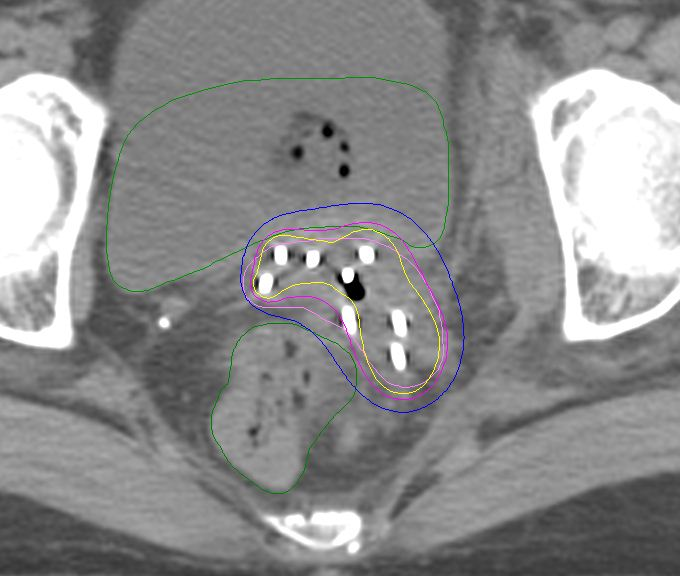

我们治疗上首先对患者进行模拟定位,制定出3D打印虚拟计划并设计针道,设计患者个体化3D后装模板,并制定周密个性化的精确放疗计划。麻醉科进行麻醉评估无禁忌症后,在B超实施超声引导给予患者行3D后装模板插植施源器植入。

后予患者行定位CT扫描,调整插值针位置深度,实时勾画三维后装靶区,放疗物理师制定出放疗计划,验证计划核查无误后,后装技师开始实施后装放疗。

目前后装放疗技术经过数十年发展,已由二维后装治疗发展到三维后装放疗和四维自适应近距离后装放疗。二维后装治疗基于X线摄片进行靶区勾画,缺乏对肿瘤靶区和正常器官的精确定位,治疗精确性和个体化性差,无法准确评估肿瘤靶区和正常器官的照射剂量,故不良反应也较大。三维/四维后装治疗是基于CT/MRI引导下的后装治疗,能够根据每次治疗时肿瘤及正常器官的变化情况准确评估肿瘤靶区和正常器官的照射剂量,在提高治疗效果同时降低不良反应,是国内外目前最先进和常用的后装治疗方式,其中,3D打印个体化共面/非共面模板引导下的后装插植治疗,是目前最精确个体化的后装治疗技术。